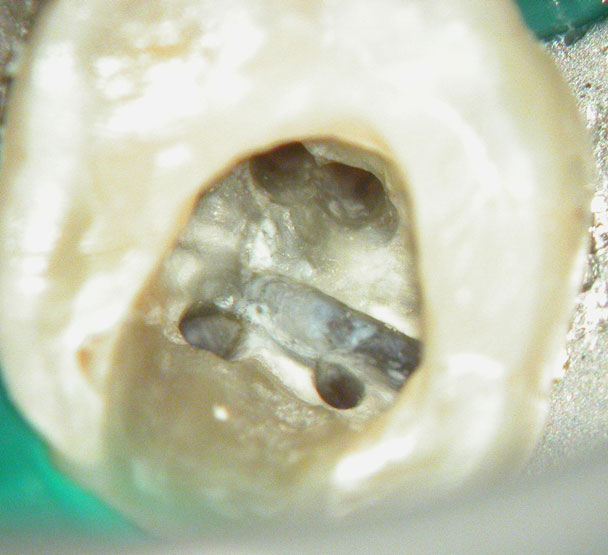

Clinical Case

Naso-Palatine Cyst misdiagnosed + Calcified Canal + Broken Instrument

• This was a Naso-palatine cyst mis-diagnosed as a lesion of endodontic origin

• Treatment was started by the previous clinician and referred to our clinic.

• Referred for:

a) removal of broken instrument in the left maxillary central incisor

b) Location of calcified canal in the right maxillary central incisor

Pre-op

Calcified canal (Red arrow), Broken instrument (Yellow arrow)

Right Maxillary incisor: CBCT shows that canal is under the palatal wall of the access cavity.

Canal located

Right maxillary incisor cleaned, shaped and obturated.

Fractured instrument in the left maxillary incisor.

Fractured instrument by-passed

Pre-op & Post-op